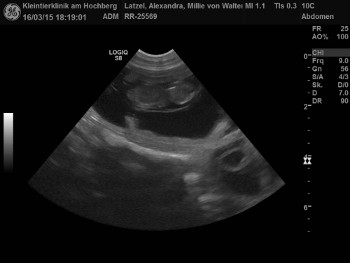

| 06. und 07.03.2015 |

|

Aennchen war am 6. und 7. März zum Decken bei Homer. Aus dieser Verbindung gehen sechs Welpen hervor, wie das Ultraschallbild zeigt. |